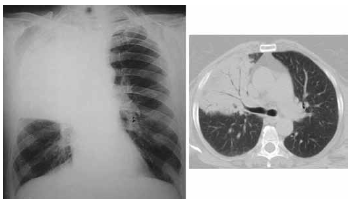

Paciente do sexo masculino, 42 anos, tabagista, etilista de 1 litro de destilado por dia, procura atendimento médico com queixa de tosse com expectoração esverdeada há cerca de 6 dias. Associado ao quadro relata inapetência, febre de até 40 graus concomitante a calafrios e tremores. Encontra-se, ao exame físico, desidratado, taquipneico leve, PA 120x70 mmHg, FC 102 bpm, temperatura = 38 ºC e saturação de O2 = 90%. Realizadas radiografia de tórax e tomografia computadorizada de tórax que estão ilustradas a seguir.

O agente etiológico mais provável envolvido no diagnóstico desse paciente é o(a)

A propedêutica pulmonar desse paciente provavelmente revelará: